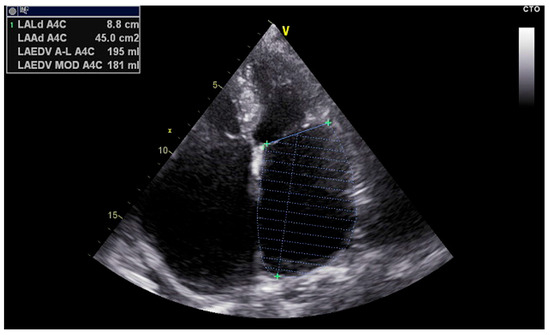

| LAVI | Left Atrial Volume Index |

| LAVI (Volume Index) | Indicates chronic structural remodeling and LA dilation due to volume/pressure overload | Correlates with widespread CFAEs, multiple breakthrough sites, and complex activation patterns |